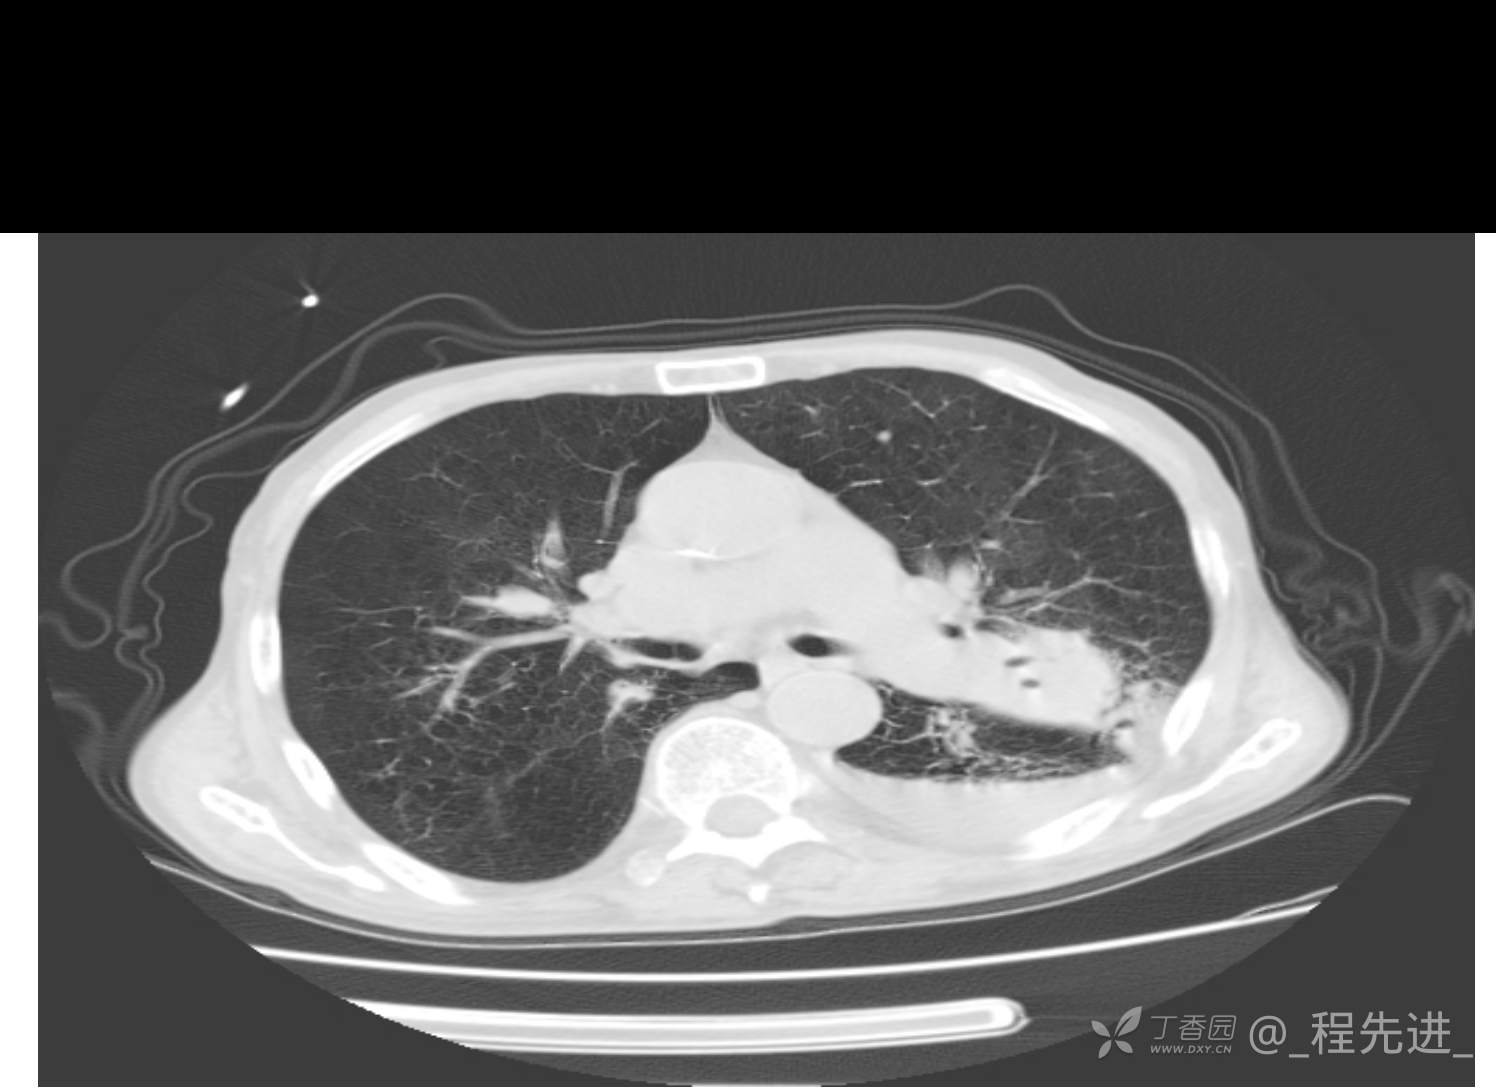

患者性别:男

患者年龄:81岁

简要病史:反复咳嗽、咳痰20余年,加重1周。两肺呼吸音低,可闻及散在干湿啰音。